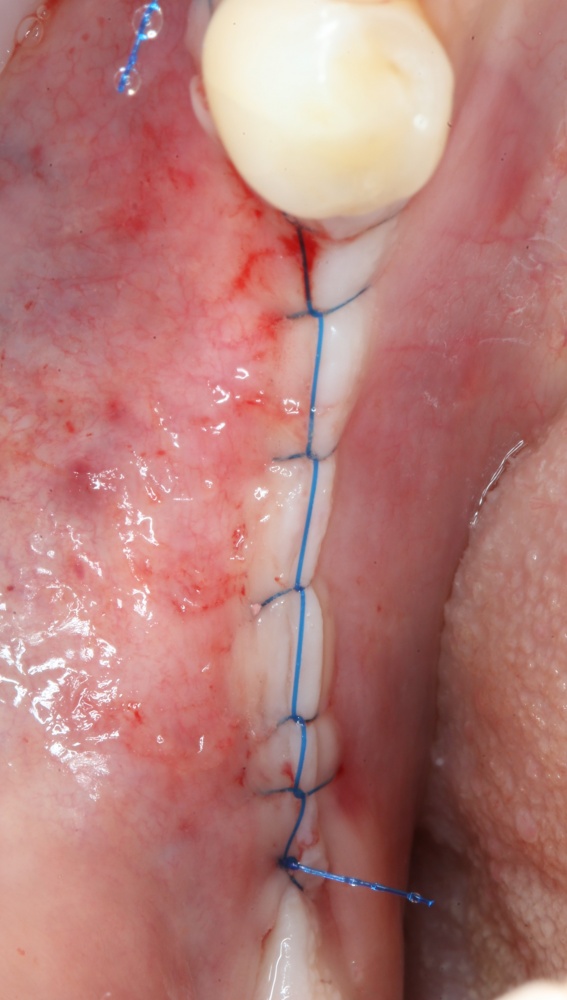

9. Наложение швов.

Я ни разу не испытывал каких-то проблем с ушиванием операционной раны. Как правило, её края сходятся достаточно легко без дополнительной периостотомии. Для наложения швов мы используем монофиламентные нерезорбируемые нити диаметром 5-0 (Resolone, Prolene, Полипропилен и др.).

Швы можно снять на 10-14 день.